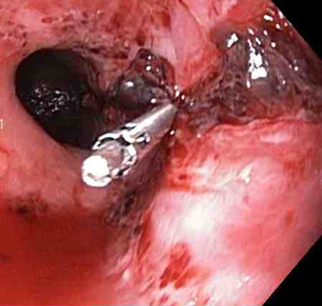

Os clipes do tipo "through-the-scope" (TTSC), isolados ou em combinação com injeção de adrenalina, podem controlar efetivamente lesões com sangramento ativo; os clipes são tão eficazes e seguros quanto outros métodos.[74][75][76] De acordo com a experiência dos autores, esta é a técnica de escolha em pacientes com laceração ou ruptura com sangramento ativo. A aplicação de TTSCs e ligadura com nó de forca no esôfago também foi descrita como um método para fechamento de grandes lacerações de Mallory-Weiss.[77][Figure caption and citation for the preceding image starts]: Um clipe do tipo "through-the-scope" instalado no centro da lesão (sem infusão prévia de adrenalina, neste caso)Do acervo de Juan Carlos Munoz, MD, University of Florida [Citation ends].